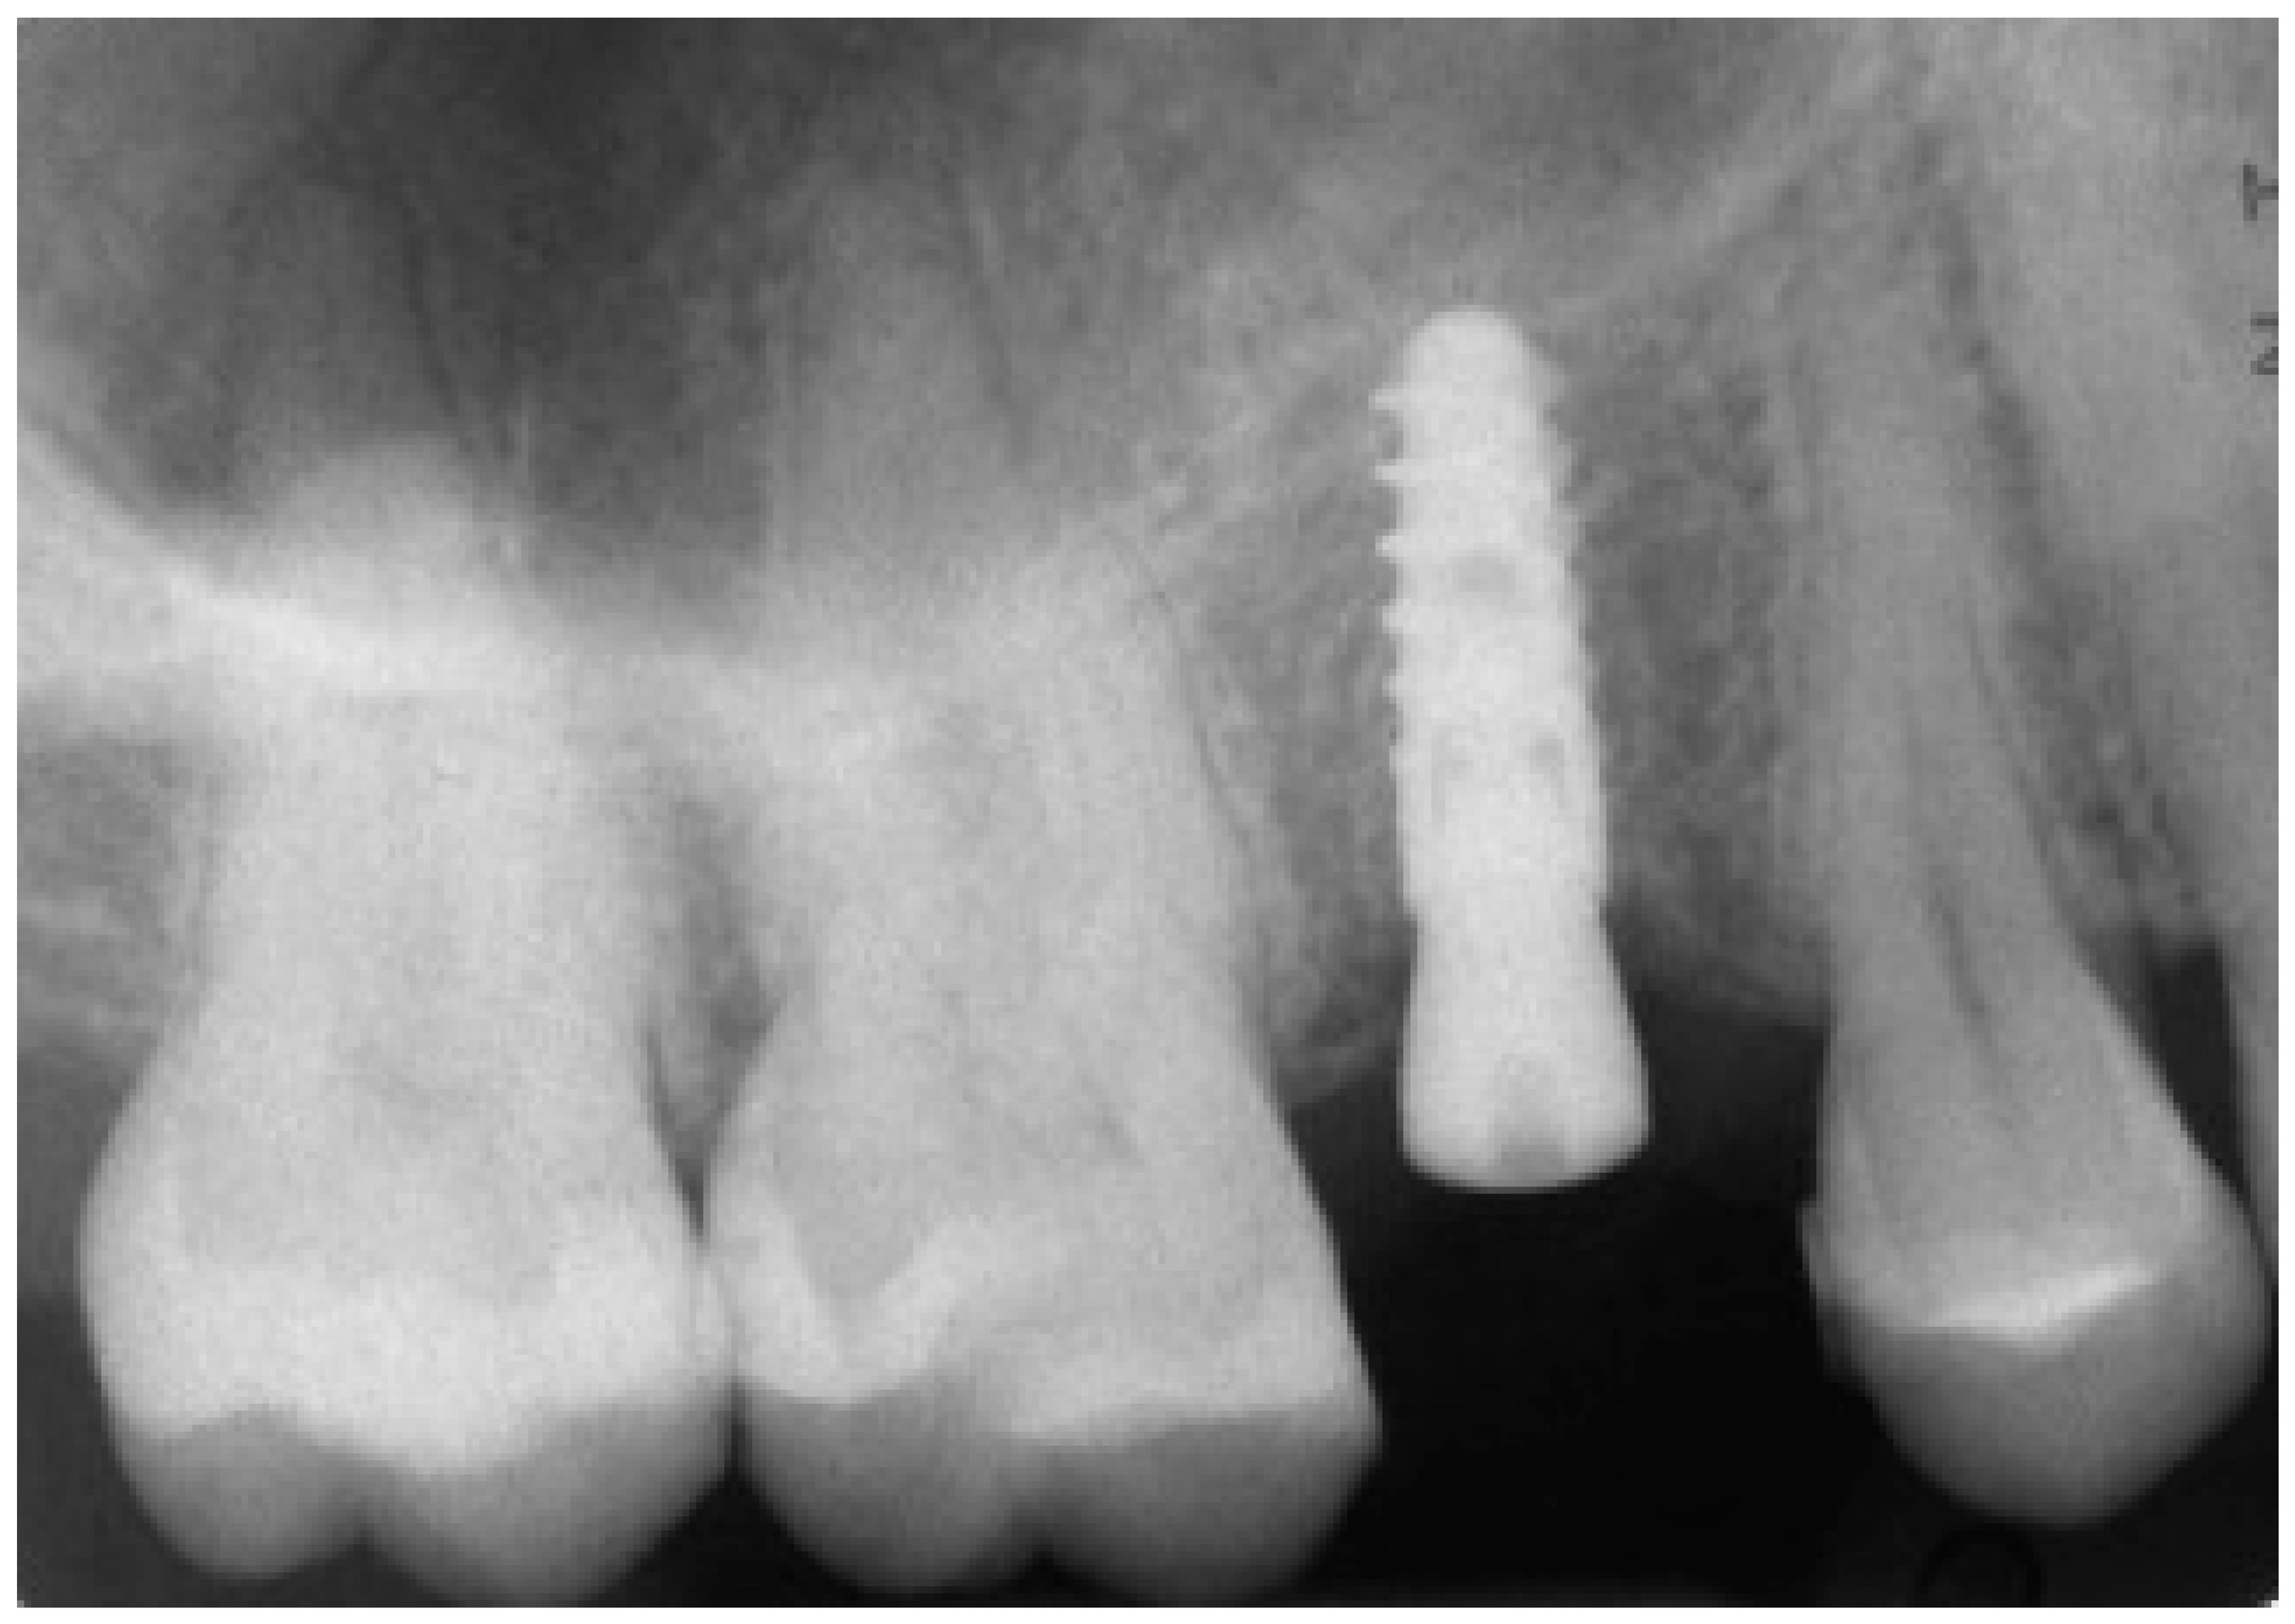

The implant was initially inserted through the handpiece, set with a maximum insertion torque of 30 Ncm; exceeding this threshold, the surgeon proceeded manually for better control. At the end of the insertion, the surgeon proceeded to remove the template and check the implant axis with a dedicated instrument, then placed a transmucosal healing screw of such height as not to be covered by mucosa during the healing phase (Figure 10).

Figure 10.

Post-surgical rx control of the implant and healing abutment.

The operation was completed and the patient was left to go home with the indication to perform 3 or 4 mouthwashings with chlorexidine 0.2% within 4 days after the operation, and with a prescription of painkiller to be taken when needed (ibuprofen 600 mg, maximum 2/day). Since no sutures were placed, the first follow-up visit was set at 10 days after the intervention.